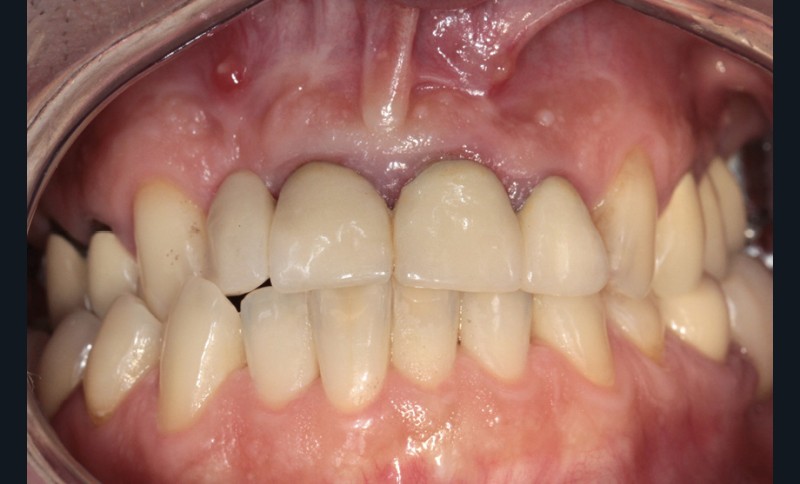

L’examen endobuccal montre deux fistules en regard des apex de 12 et 21 (fig. 1). Nous notons la présence d’une classe III squelettique, d’une occlusion inversée du côté droit (fig. 2) et des édentements non compensés au niveau de 26 et 36. L’orthopantomogramme révèle la présence d’une volumineuse lésion kystique qui s’étend de la 12 à la 22 (fig. 3).